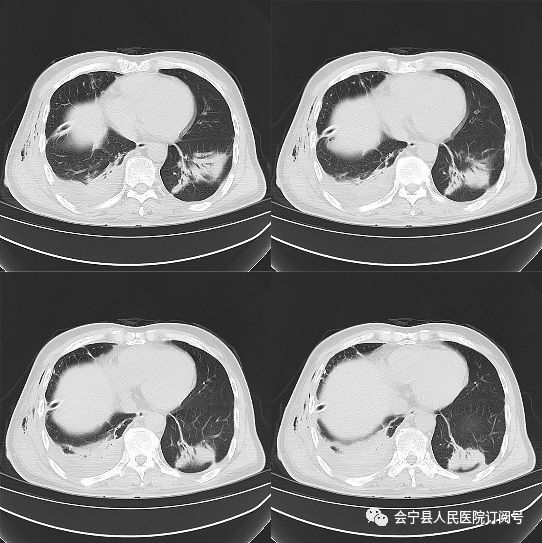

大量自发性血胸你见过吗│以影识病

会宁县医院6名医师简历